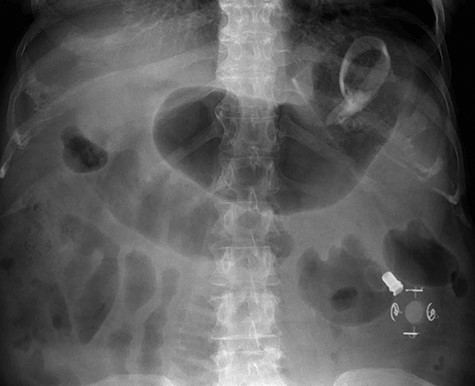

A 59-year-old female presented to the emergency department with a 2-week history of progressive central abdominal pain and distention on a background history of a laparoscopic adjustable band insertion 11 years previously. She had associated nausea, vomiting and denied dysphagia, odynophagia, or change in bowel habit. Clinically, she was afebrile, tachycardic, and on examination, displayed diffuse abdominal tenderness and guarding. Inflammatory markers were mildly elevated (white cell count 13.7 × 109/L, C-reactive protein 105 mg/L), and a moderate hyperlactatemia was observed (lactate 2.4 mmol/L). A plain film abdomen demonstrated a distended, air-filled stomach (Fig. 1). Subsequent computed tomography of the abdomen and pelvis demonstrated an intragastric band erosion with the internalization of the entire gastric band and distal connector tubing within the gastric lumen (Fig. 2). Moderate free fluid and ascites were noted with considerable mesenteric inflammatory fat stranding. The portal vein was non-opacified, indicating a possible portal vein thrombosis (PVT).